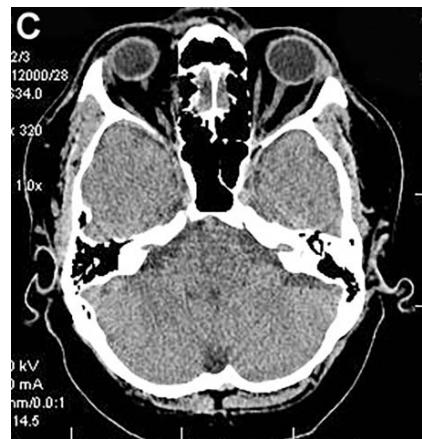

Figure 3: Same patient S., 42 years old, male.

A. Cerebral CT before transcatheter intracerebral laser PBMT: Total atrophy of the temporal lobes is $18\%$ of the total tissue volume (TDR-1). B. Cerebral CT in 12 months after transcatheter intracerebral laser PBMT: total atrophy of the temporal lobes decreased to $9\%$ of the total tissue volume (TDR-1). C. Cerebral CT in 4 years after transcatheter intracerebral laser PBMT: total atrophy of the temporal lobes decreased to $5.5\%$ of the total tissue volume.

The patient is transferred to AD group in TDR-0 stage.

According to the results of digital processing of CT and MRI images one year after the treatment, all 16 (100%) patients had an 8-10% decrease in the temporal lobes atrophy (Figures 3A, 3B). After 2-4 years, 13 (81.25%) patients showed a further 4-5.5% decrease in the temporal lobes atrophy leading to an almost complete restoration of the temporal lobe volume to the age norm (Figure 3B, 3C). Narrowing of the Sylvian fissures and restoration of the subarachnoid space accompanied the process. In accordance with the abovementioned criteria, all 16 (100%) patients were transferred to Group TDR-0.